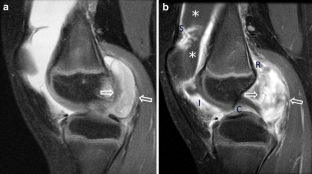

Fig. 4